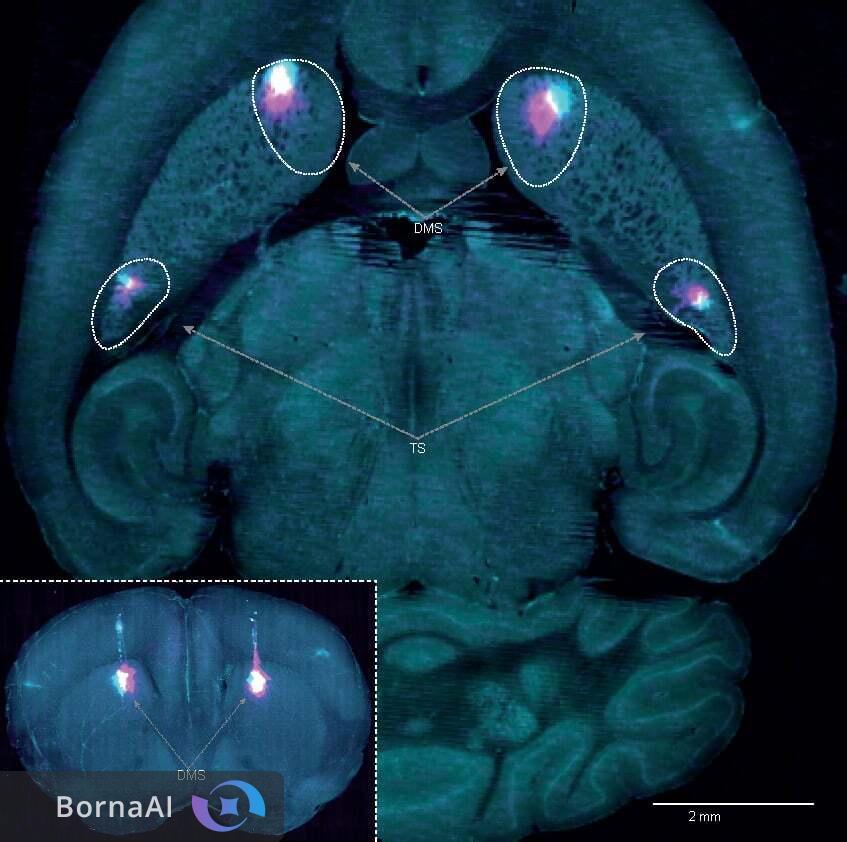

اما در مطالعهی جدید، محققان نوع دوم سیگنال دوپامین به نام خطای پیشبینی عمل (Action Prediction Error - APE) را شناسایی کردند. این سیگنال بر اساس تکرار یک عمل خاص فعال میشود، بدون توجه به نتیجهی آن. به عبارت دیگر، APE به مغز اجازه میدهد تا الگوهای رفتاری تکراری را بدون ارزیابی مداوم ارزش آنها ذخیره کند.

در بیماری پارکینسون، نورونهای دوپامین مرتبط با حرکت در ناحیهی "substantia nigra pars compacta" از بین میروند. این نورونها ممکن است مسئول کدگذاری سیگنال APE باشند. از دست دادن این نورونها میتواند توضیح دهد که چرا بیماران در انجام رفتارهای عادی مانند راه رفتن دچار مشکل میشوند، اما در انجام رفتارهای انعطافپذیرتر مشکلی ندارند.